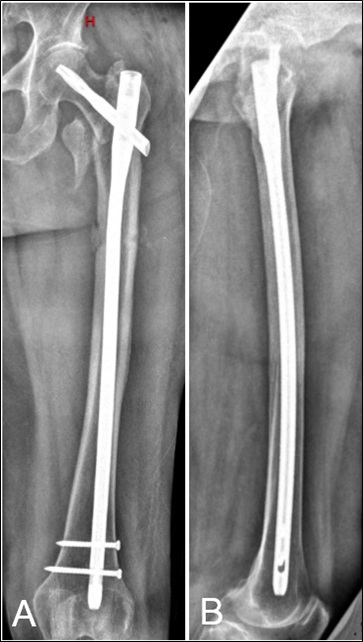

Penetración de la cortical anterolateral en fracturas de fémur proximal tratadas con clavos endomedulares cortos Reporte de dos casos. [Penetration of anterior-lateral cortex in proximal femur fractures treated with short intramedullary nails Report of two cases].